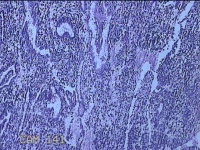

宫腔内容物

性别

女

年龄

47岁

临床诊断

1.异常子宫出血 2.慢性宫颈炎

一般病史

不规则阴道流血21天。

标本名称

大体所见

灰白暗红色不规则碎组织2.5x1.8x0.3cm一堆。

图4